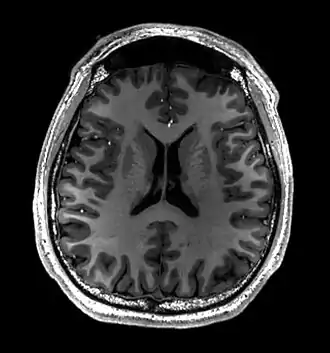

Cross-sectional T1-weighted MRI of a healthy human brain acquired with an ultra high-field MR of 7 Tesla field strength | |

- T1-weighted (T1W) images: Cerebrospinal fluid is dark. T1-weighted images are useful for visualizing normal anatomy.